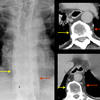

paraspinal interface